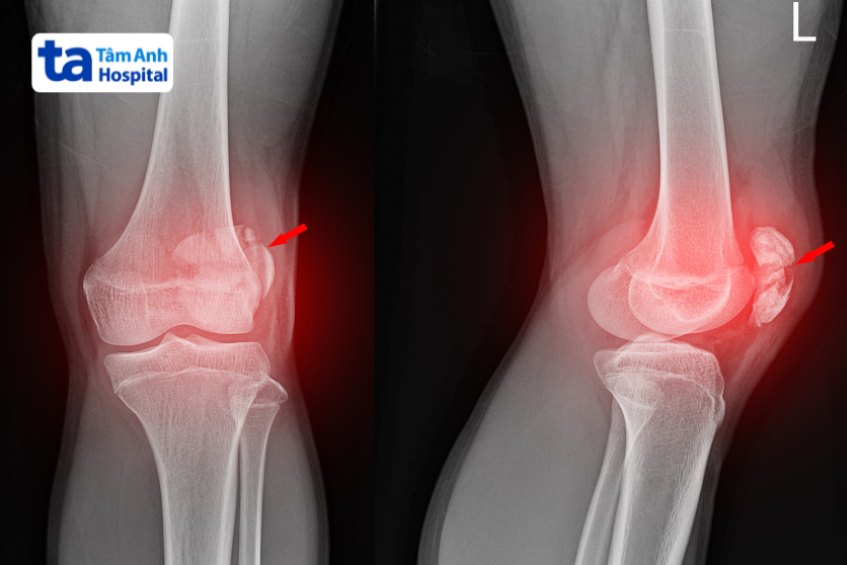

Trật xương bánh chè xảy ra do cầu thủ thực hiện các động tác đổi hướng đột ngột khi đá bóng, khiến xương bánh chè bị trượt ra khỏi rãnh lồi cầu xương đùi.

Gãy xương vùng gối hay gãy xương đùi, xương chày, xương bánh chè là hiện tượng ít gặp trong bóng đá, thường xảy ra khi vận động viên bị ngã đập đầu gối, co cơ tứ đầu đùi đột ngột…